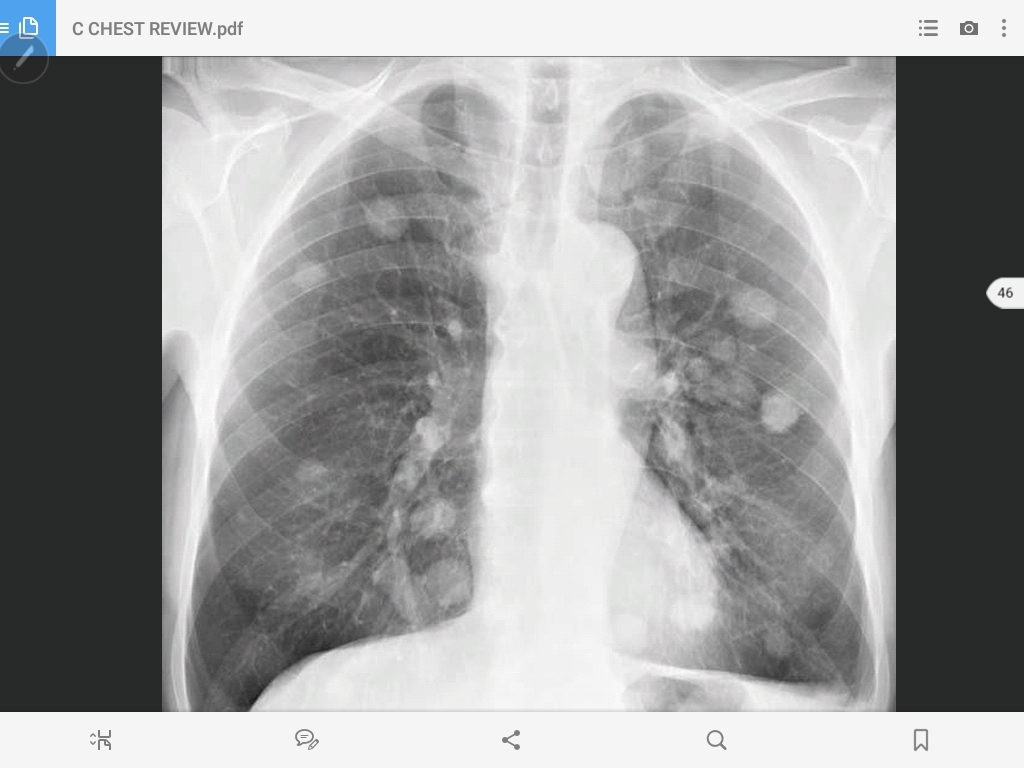

pulmonary metastasis